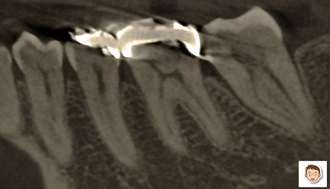

先程、インテックス大阪で日本デンタルショーが開催されました。各メーカーが、新たに開発した新商品を発表、展示するショーといったところです。(株)ヨシダもその中の一つでした。左の写真は、歯を2D(平面)や3D(立体)にレントゲン分析する機械です。以前に比べ、より画質が細かく、鮮明になっていたことに驚きました。これなら、歯を削らず、または歯茎を切らずにして、より正確な診査・診断が可能となります。

左は、一般的なレントゲン像。この平面画像をみて、歯を立体的にイメージし、治療に取り組むことが歯科医の役割でしたが…。

CTで撮影した歯をパソコンで分析。縦割り、横割りにされた歯の断面が次々と画面に表れてきます。また、がい骨?のような茶色の画面からは、歯周病で失われた骨の量や場所が表示されます。

左の3D画像からは、虫歯の大きさ、失われた骨の量、神経が走行している位置など様々な情報が入ってきます。